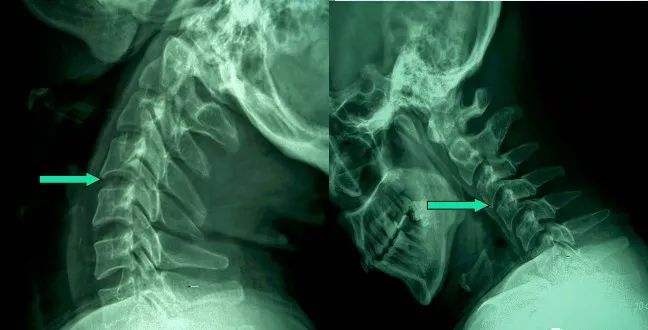

1、頸椎移位

由于頸椎關節(jié)突間關節(jié)面近乎水平位,一旦椎間盤發(fā)生退變、椎間隙即變窄,關節(jié)囊及韌帶松弛,加上頸部活動時重力的影響,即可造成積累性損傷,加速頸椎退變和不穩(wěn),導致頸椎關節(jié)發(fā)生移位,使椎間孔變狹,椎管徑發(fā)生改變,壓迫神經(jīng)根或脊髓,產(chǎn)生臨床癥狀與體征。